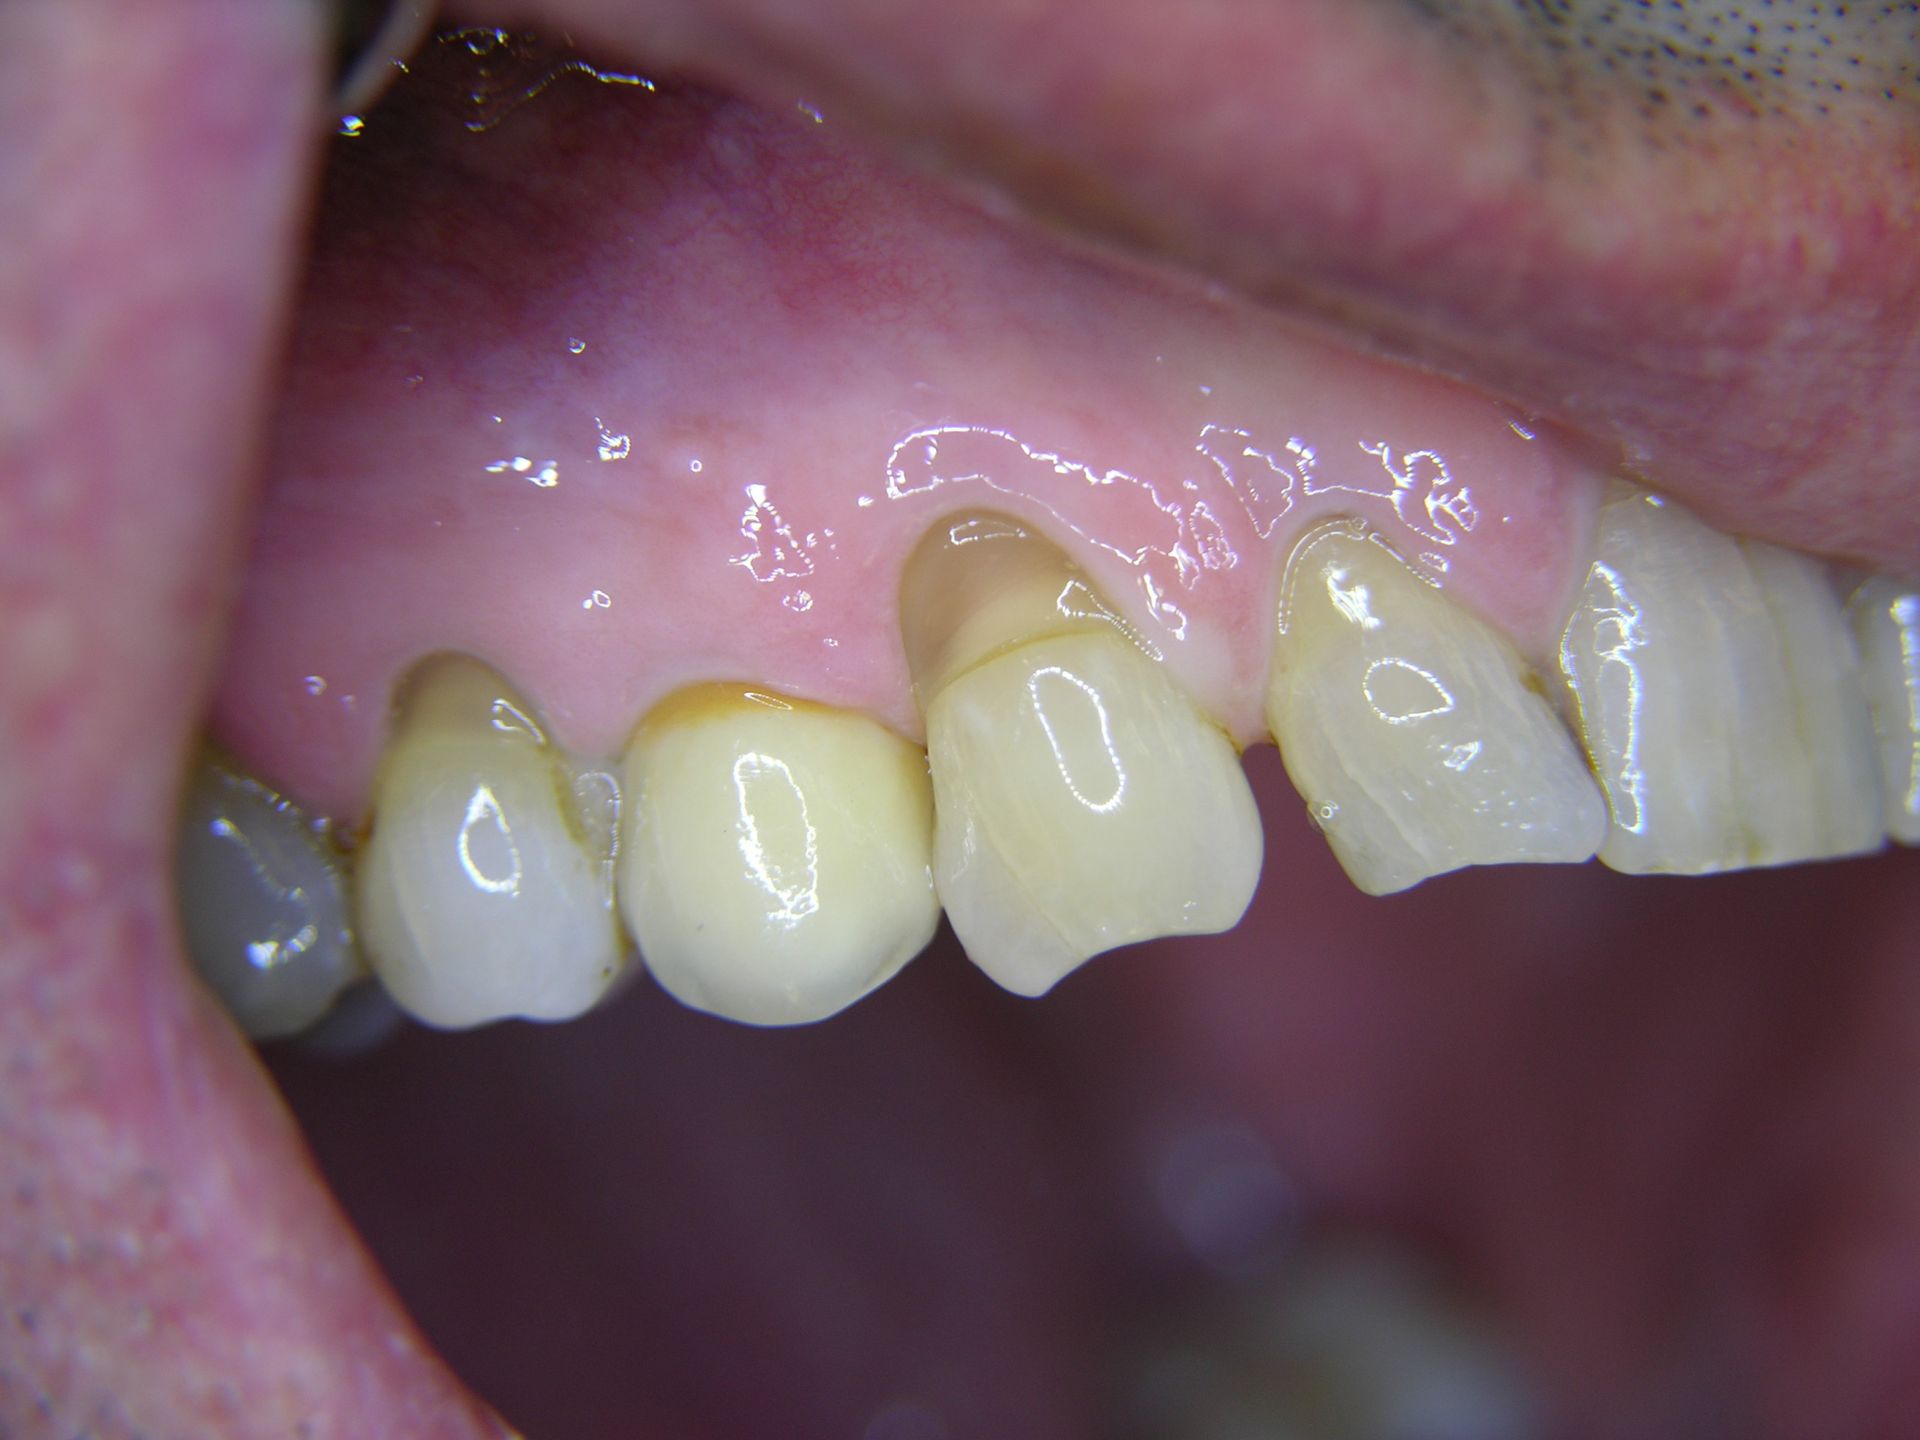

Beispiele von Versorgungen